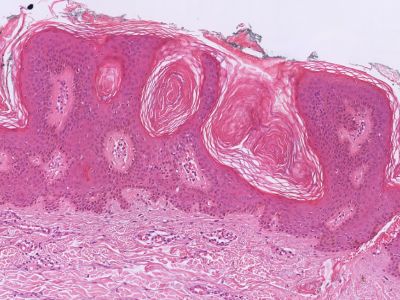

Histologie:Het histologisch beeld wordt gekenmerkt

door een scherp begrensde exofytisch of endofytisch groeiende tumor. Meestal

is er hyperkeratose en een papillomateus verbrede epidermis. De hyperkeratose

en de neiging van de retelijsten om te vergroeien, hebben de vorming van pseudo-hoorncysten

tot gevolg. De tumor is opgebouwd uit opvallend kleine spinale cellen. Basale

hyperpigmentatie is er in een derde van de gevallen. De epidermis toont geen

cytonucleaire atypie. Meestal zijn er geen afwijkingen in de dermis. In de dermis

van een geirriteerde verruca seborrhoica wordt echter een uitgebreid rondkernig

ontstekingsinfiltraat gezien met grensvlakactiviteit en soms met dyskeratotische

keratinocyten. Karakteristiek zijn de zogenaamde “squamous eddies”, nesten van

keratinocyten. Het Borst-Jadassohn type, ookwel het clonale type, is te herkennen

aan intra-epidermale nesten van spinale cellen.